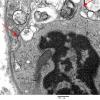

PERIPHERAL NEUROPATHY

4 AXONAL DEGENERATION

4 Macrophages